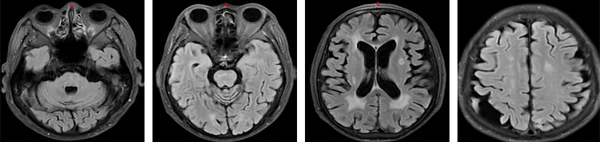

治疗前(2020年6月)

治疗5年(2025年6月)